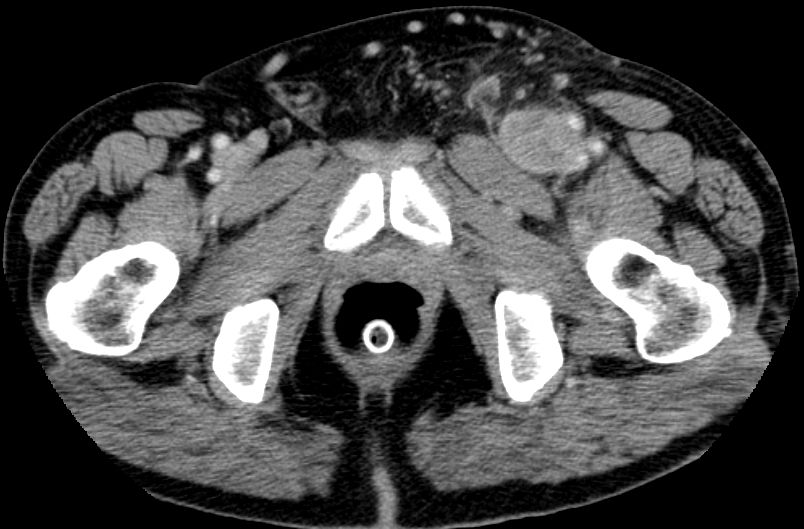

| Leiste | 72-jähriger Landwirt mit einem Leiomyosarkom der linken Leiste pT2b pN0 G2 R0. 110 x 50 x 50 mm großer, solider Tumor mit enger Lagebeziehung zum Gefäßbündel.

Infiltration des Musculus rektus abdominis.![]() |

![]() |

![]() | ||